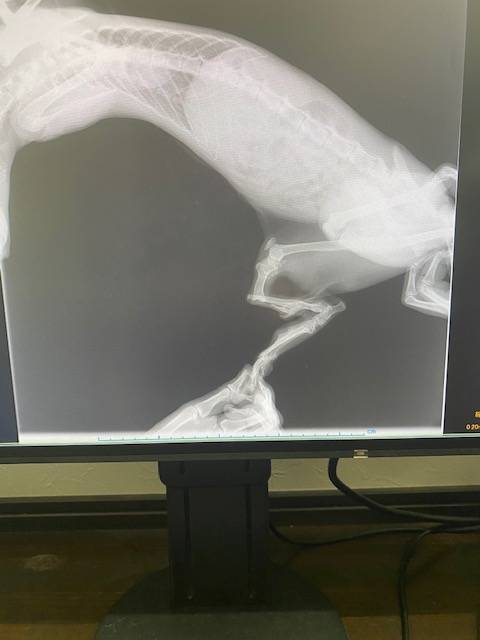

そしてMAU母のレントゲンの写真を夕方見せてもらい絶句。。。

骨折し、変な形で固まってしまい固まった部分の皮膚と皮膚が癒着し化膿していたとのこと・・・・・